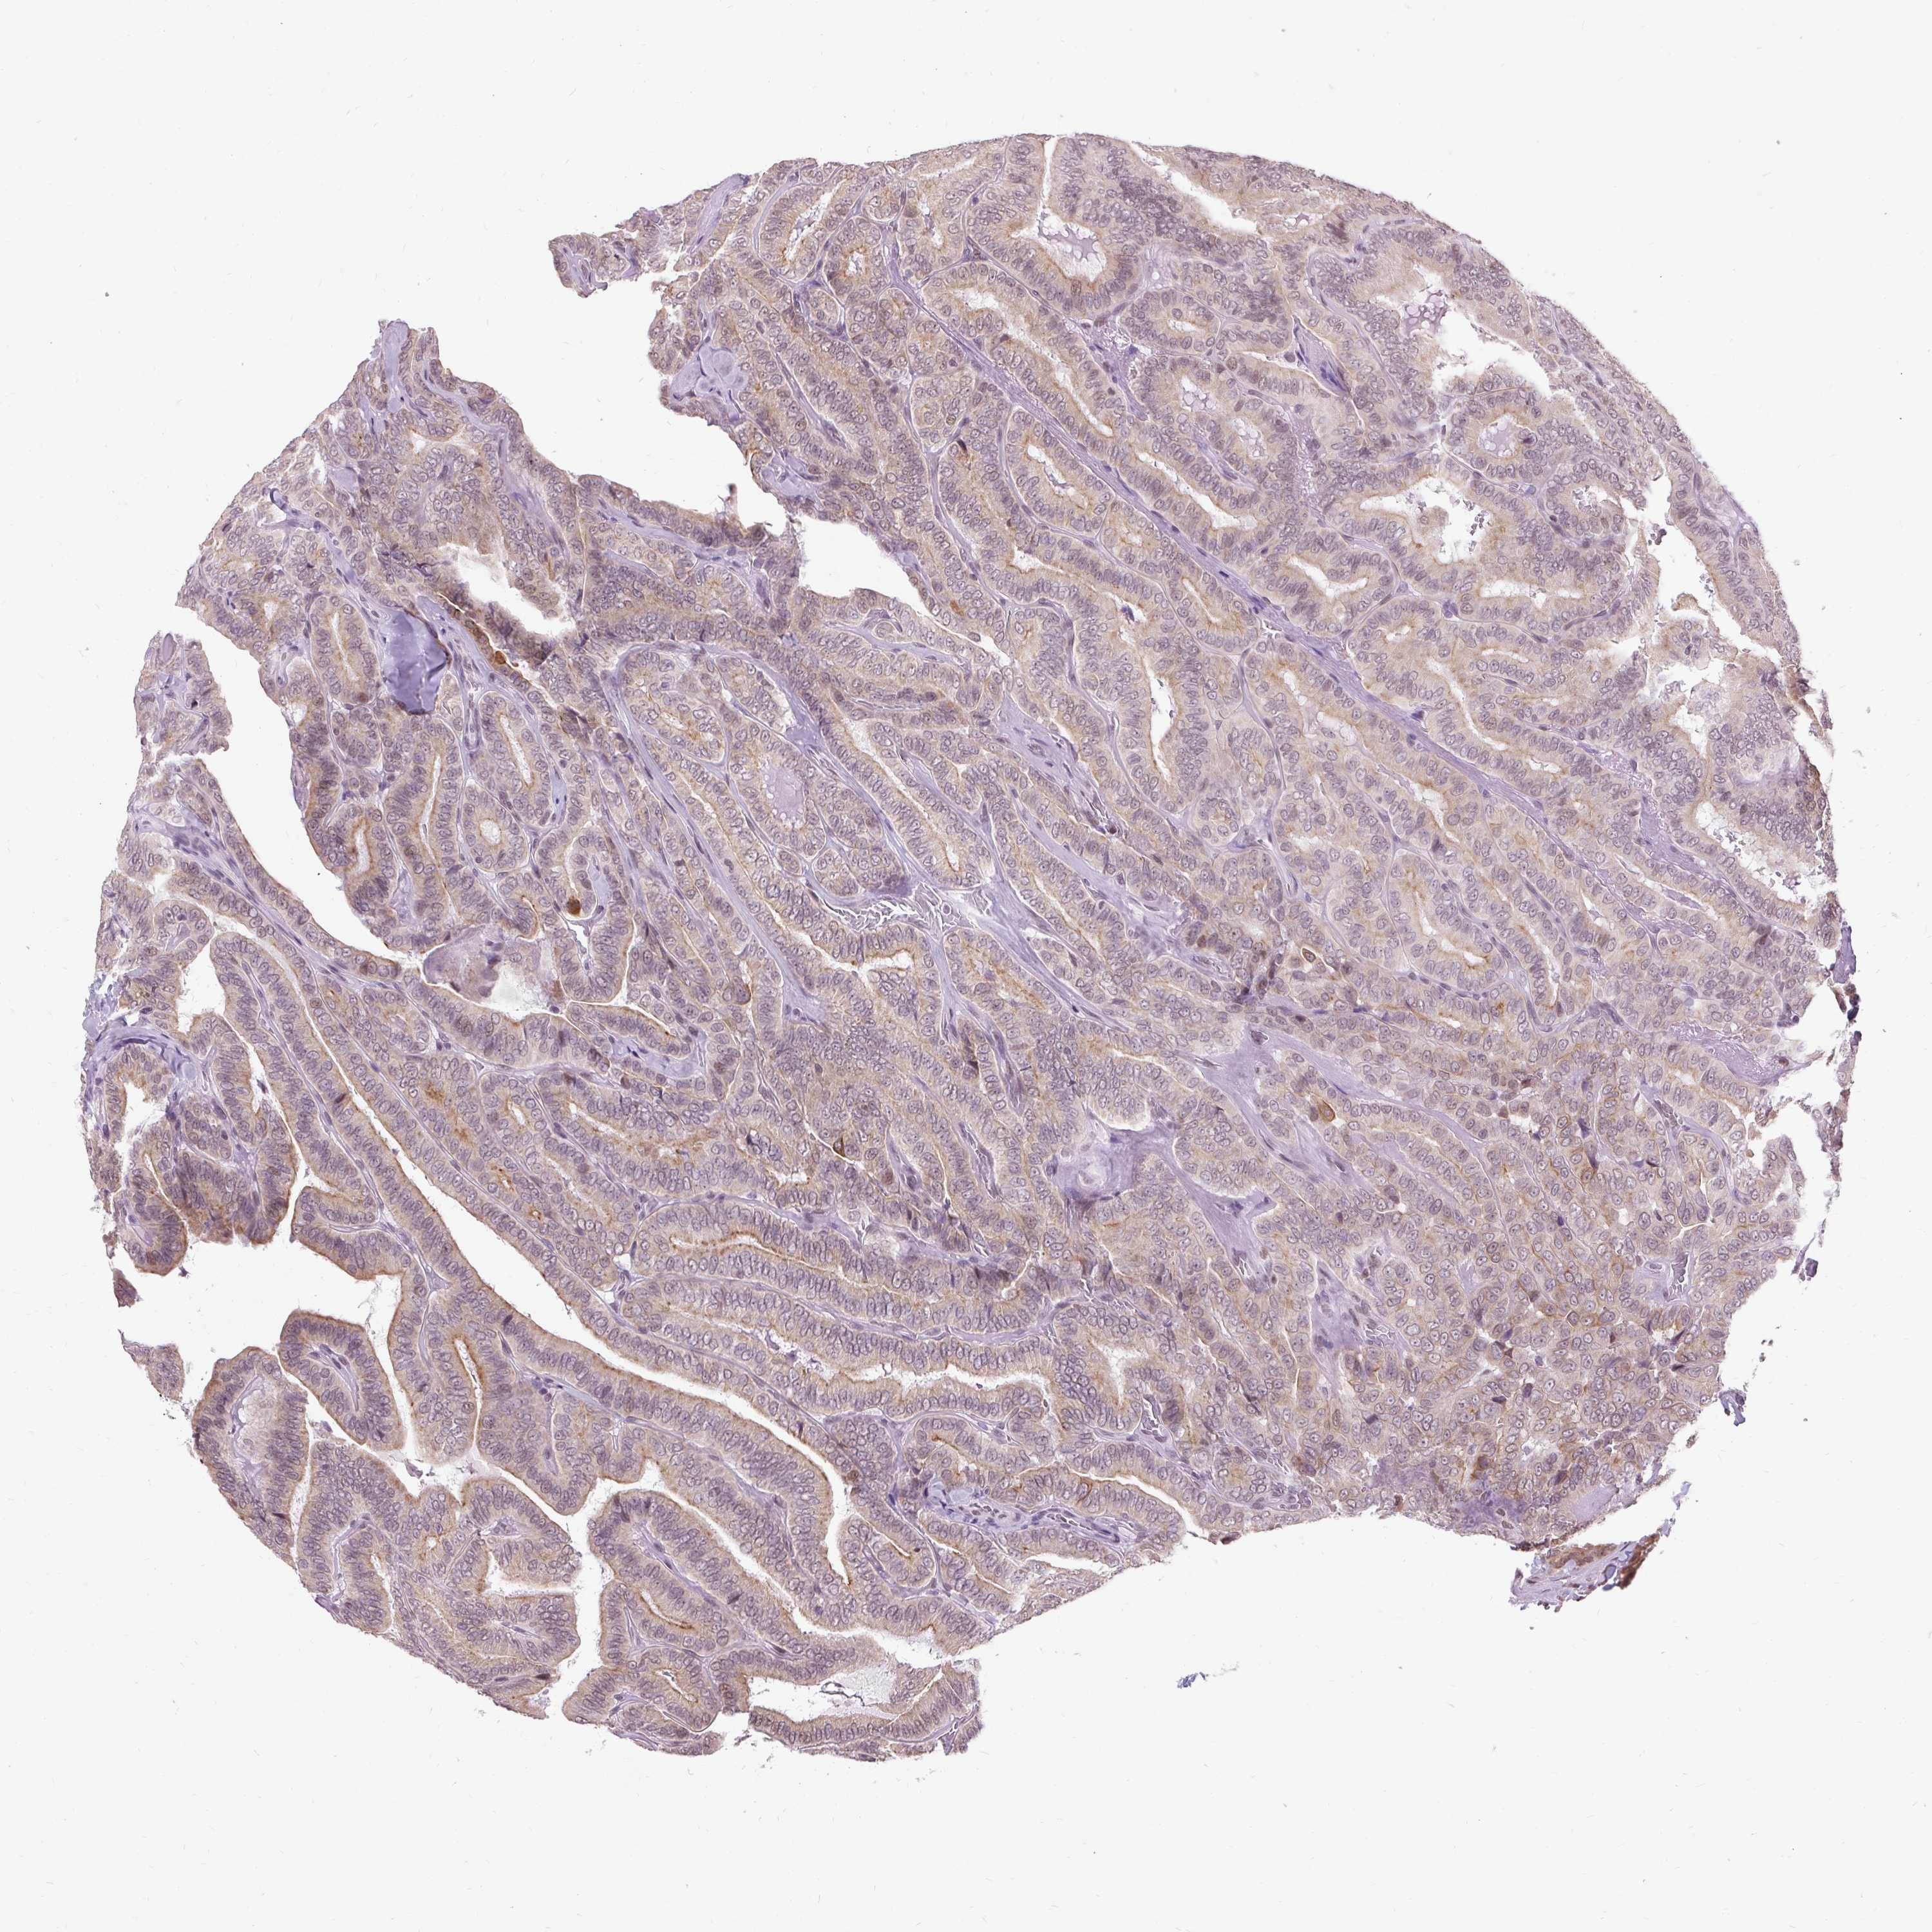

THYROID CANCER - Protein expressioni

A mouse-over function shows sample information and annotation data. Click on an image to view it in a full screen mode. Samples can be filtered based on level of antibody staining by selecting one or several of the following categories: high, medium, low and not detected. The assay and annotation is described here.

Note that samples used for immunohistochemistry by the Human Protein Atlas do not correspond to samples in the TCGA dataset.

Antibody stainingi

Antibody staining in the annotated cell types in the current human tissue is reported as not detected, low, medium, or high, based on conventional immunohistochemistry profiling in selected tissues. This score is based on the combination of the staining intensity and fraction of stained cells.

Each image is clickable and will lead to virtual microscopy that enables deeper exploration of all samples and also displays staining intensity scores, fraction scores and subcellular localization as well as patient and tissue information for each sample.

Antibody HPA055779

Staining

High

Medium

Low

Not detected

Intensity

Strong

Moderate

Weak

Negative

Quantity

>75%

75%-25%

<25%

None

Location

Nuclear

Cytoplasmic/membranous

Cytoplasmic/membranous,nuclear

Papillary adenocarcinoma, NOS

Follicular adenoma carcinoma, NOS